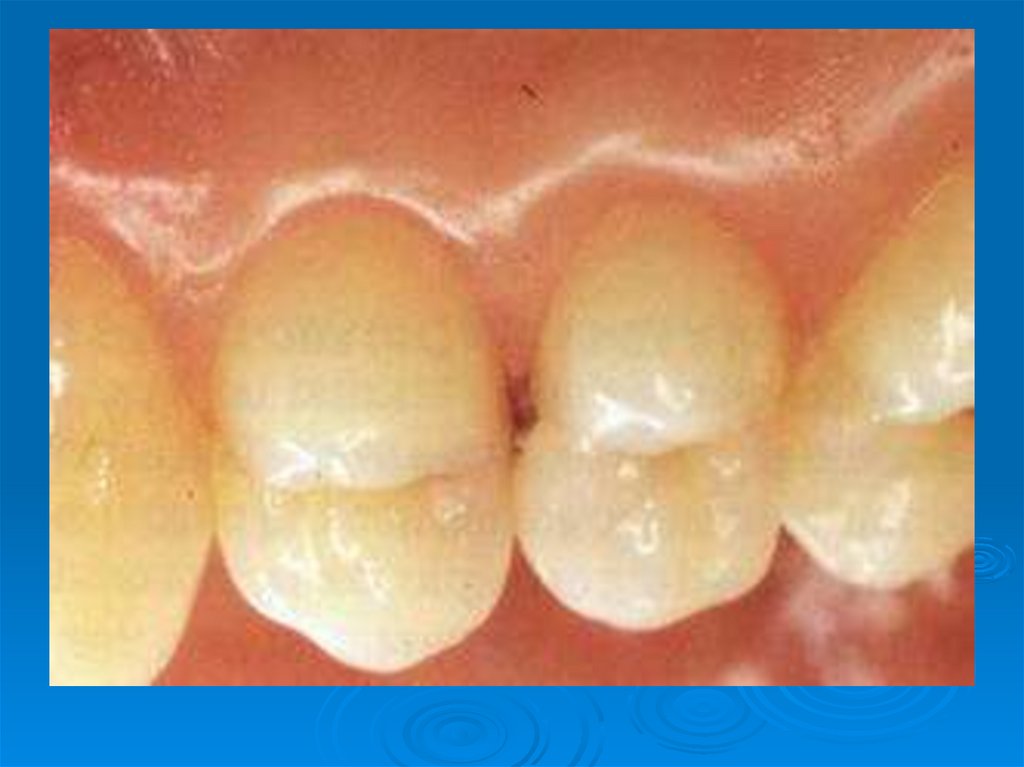

Клинические симптомы кариесогенной ситуации: плохое состояние гигиены полости рта, обильный зубной налет и зубной камень,

10. Клинические симптомы кариесогенной ситуации: плохое состояние гигиены полости рта, обильный зубной налет и зубной камень,

наличие множественных

меловидных кариозных пятен,

кровоточивость десен.